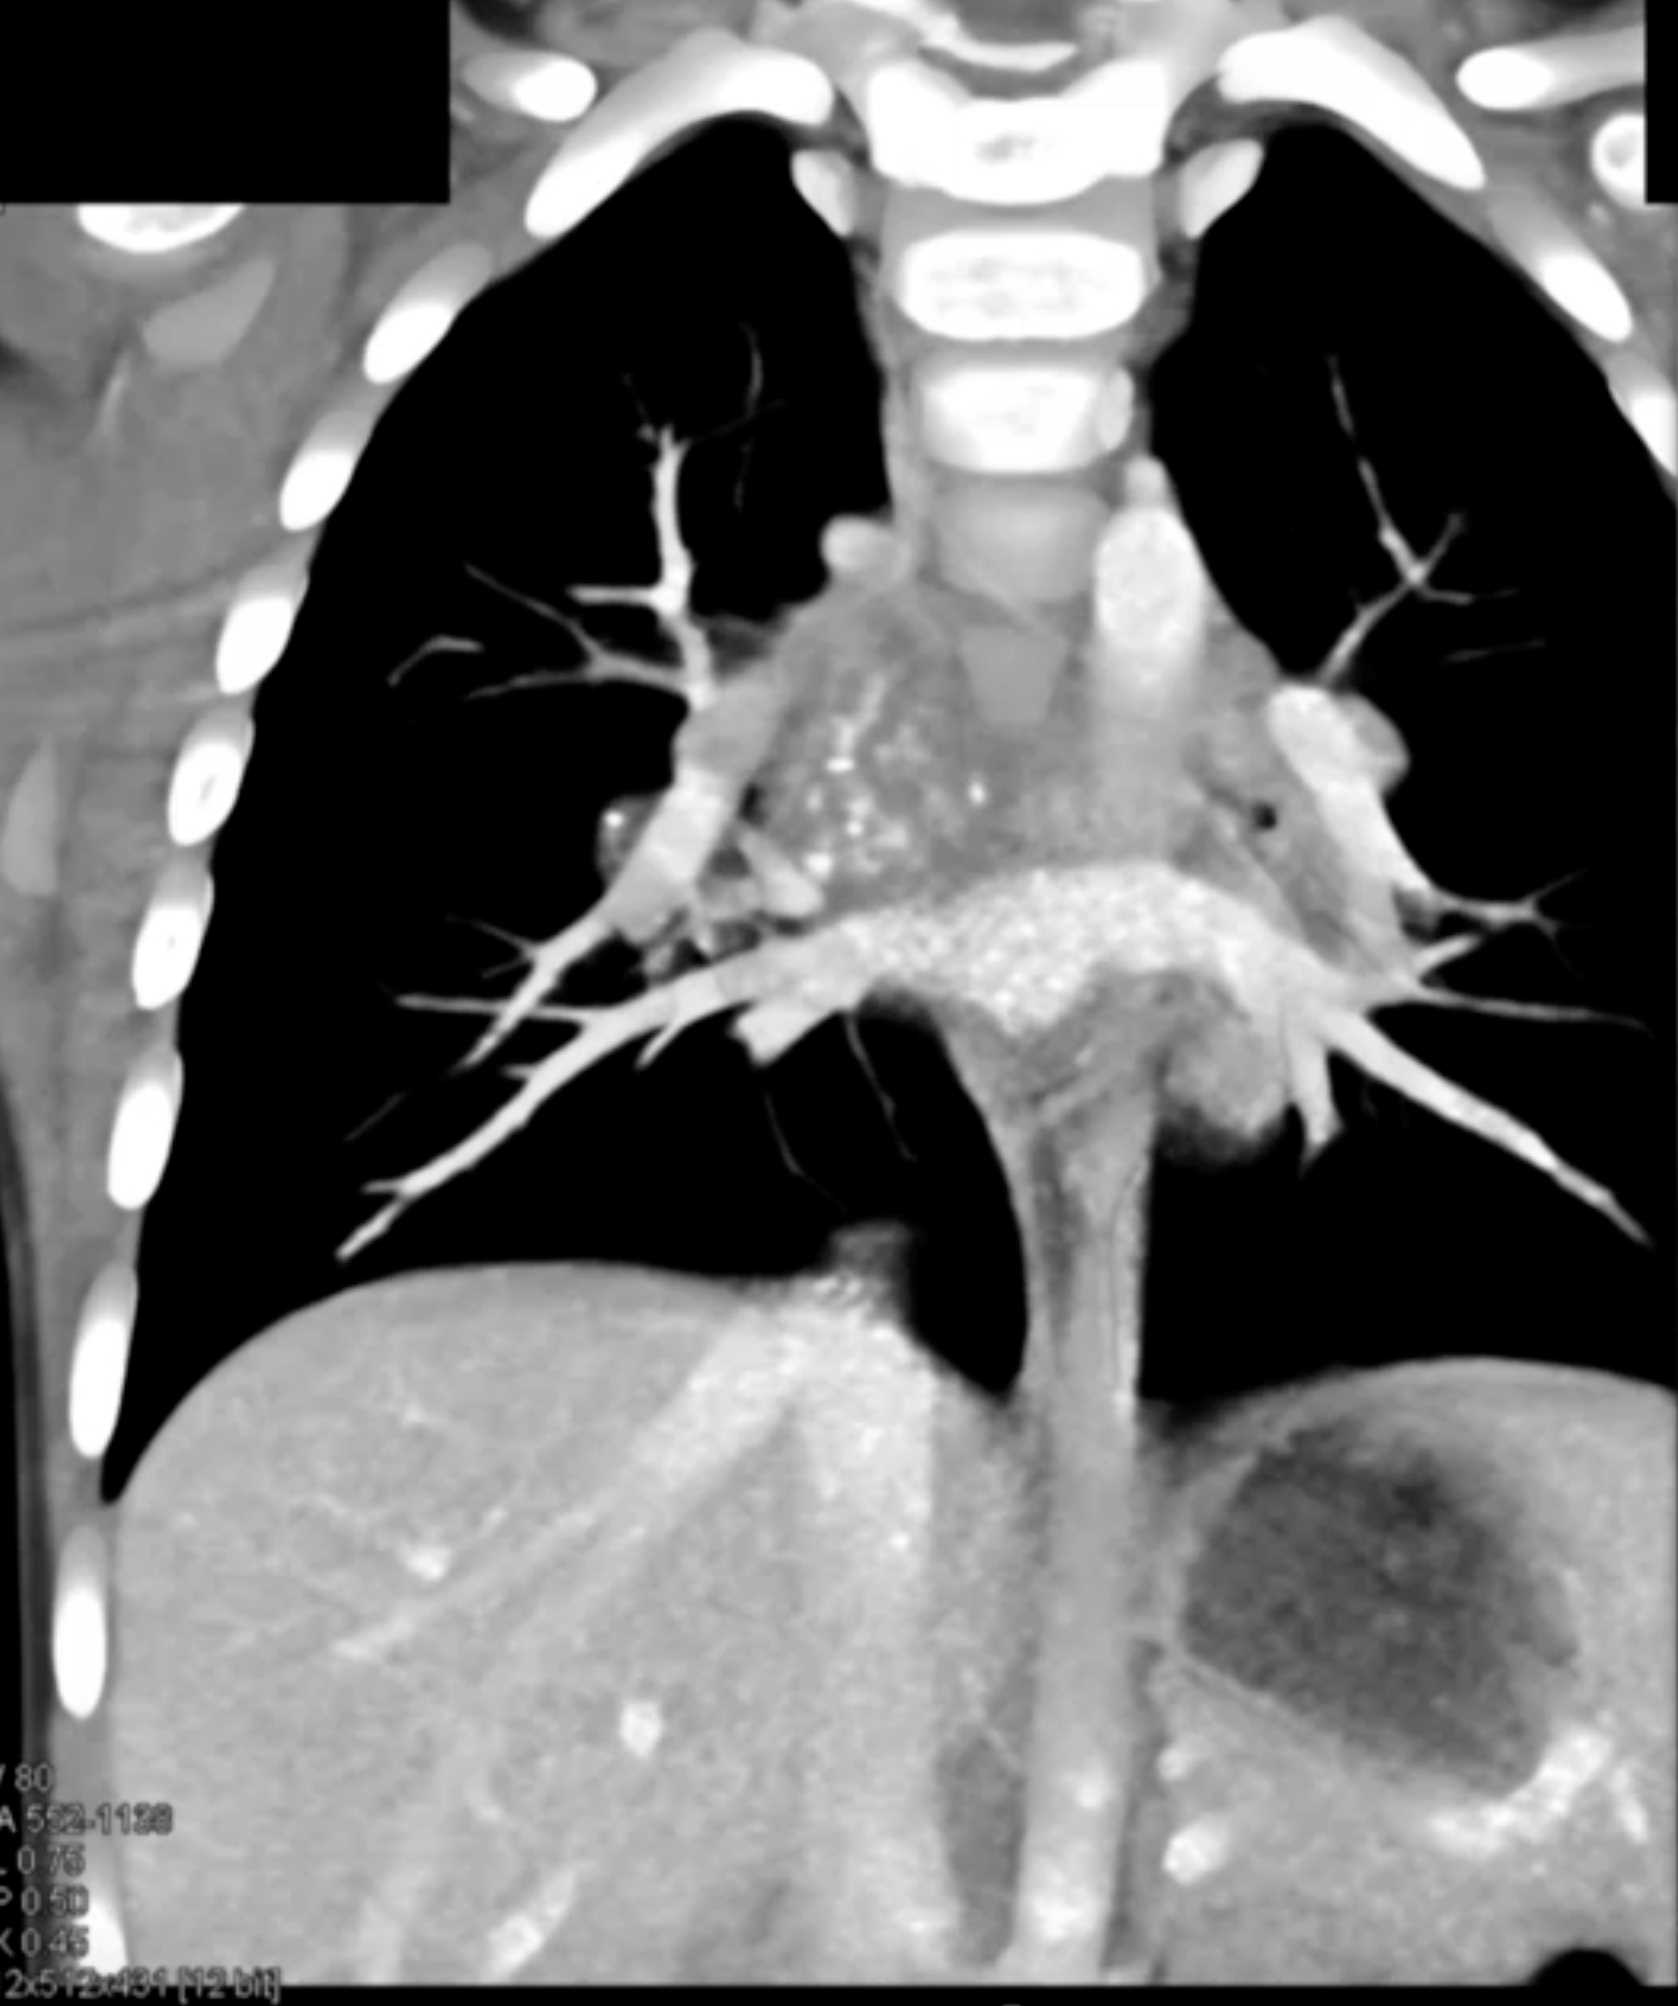

Histoplasmosis and Normal Thymus